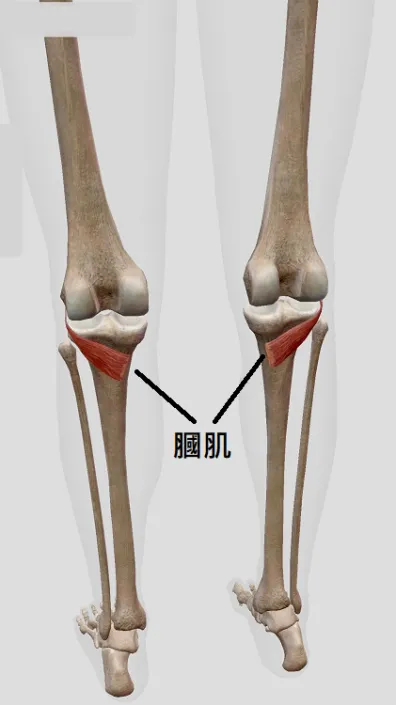

膕肌症候群 定義

膕肌症候群(popliteus syndrome) 為膕肌損傷所導致,此肌肉所擁有之感覺及動作區域產生發炎、不適症狀,即為膕肌症候群。一般常見於跑步的人,在膝蓋後外側疼痛。

整個膕肌的生長路線上,任何一個地方能壓迫或拉扯肌肉纖維的地方,都能造成膕肌症候群的問題出現。 但是並非要直接影響到膕肌,有些也能因為影響到包覆膕肌的筋膜,而造成近似膕肌症候群的症狀出現,進一步的使肌肉無法正常運作而有痛或無力緊繃等感覺。

膕肌肌肉位於膝蓋後方,而有受到意外受傷以及經常使用到此肌肉的習慣者皆屬於高風險族群。